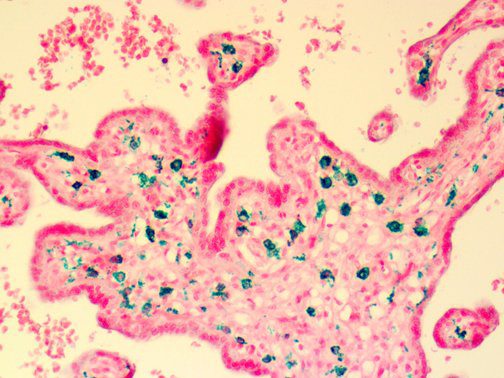

Clinical and laboratory manifestations of HLH include fever, enlarged liver and/or spleen, neurologic dysfunction, coagulopathy, liver dysfunction, cytopenias (i.e., low levels of erythrocytes, leukocytes, and/or platelets), hypertriglyceridemia, hyperferritinemia, hemophagocytosis, and eventually diminished NK cell activity as the immune system becomes progressively paralyzed. HLH can be familial (primary HLH) or secondary to another disease process (sHLH), such as rheumatic disease, in which it is referred to as macrophage activation syndrome (MAS, characterized by elevated ferritin).